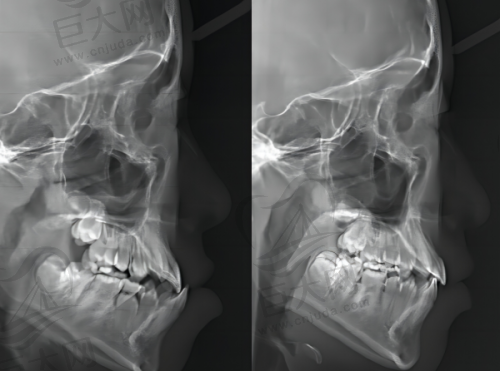

在技术方面,它有别家没有的黑科技。精细骨钉导航让骨性嘴凸不用手术,打骨钉内收5mm,侧颜杀直接逆袭;隐形矫正提速技术能让戴牙套周期缩短30%,打工人2年变1年半;咬合自适应调整杜绝了传统矫正“咬不动牛肉”的尴尬,是吃货的福音。

再看看真实实例。22岁程序员地包天矫正,金属托槽1.5万,18个月变“侧颜男神”;35岁宝妈隐形矫正3.8万,矫正期间还能接娃上班,完全隐形。